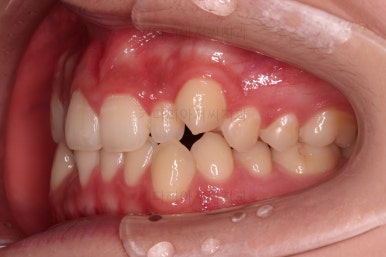

마찬가지로 초진 시 입안의 모습인데요.

위아래 앞니가 삐뚤고, 송곳니는 덧니처럼 불룩 튀어나가 있네요.

위아래 앞니는 안으로 굽어 들어와 있는 옥니(뻐드렁니 반대) 양상이었고요.

이번 부산옥니교정 환자분은 치열이 삐뚤긴 했지만, 발치라던지 통째로 밀어넣는 등의 치료가 필요할 만큼 많이 삐뚠 것은 아니었기 때문에 최대한 현재 상태에서 심플하게 가지런하게 하는데 초점을 맞추었습니다.

그리고 옥니의 경우는 시각적으로도 그렇지만 기능적이나 치아의 수명에도 문제가 되는 경우가 많기 때문에 정상적인 앞니 각도로 회복시켜주는게 필요했습니다.